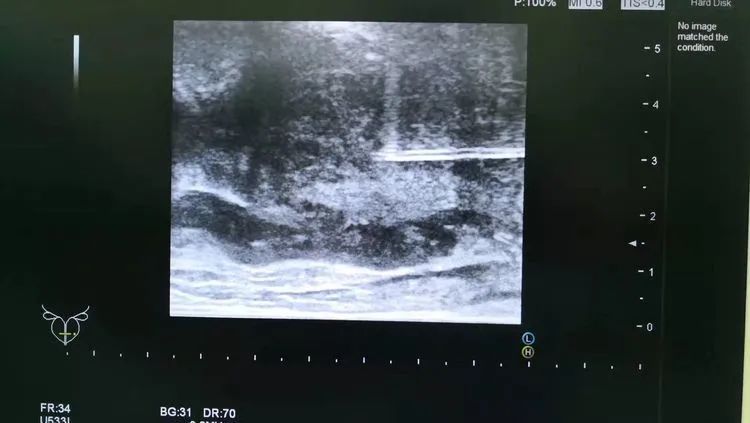

前列腺穿刺活检是通过非常细的特制穿刺针(直径1mm左右)获取前列腺组织进行病理学检查,是目前诊断前列腺癌最为有效的方法。

为更好的服务大众,淮南东方医院集团引进了国际上先进的日立阿洛卡彩超机及经直肠双平面超声探头,现已成熟开展彩超引导下经会阴前列腺穿刺活检,与北京、上海、合肥等三甲大医院成功接轨。

患者李先生,56岁,8月前发现PSA值轻度升高,先后在外院就诊数次,均未明确诊断,建议随访观察。今年2月来到淮南东方医院集团总院泌尿外科行彩超引导下经会阴前列腺穿刺活检,穿刺顺利。术后病理提示为前列腺腺癌,Gleason评分3+4。后行前列腺癌根治性切除术,术后恢复佳,现已出院。